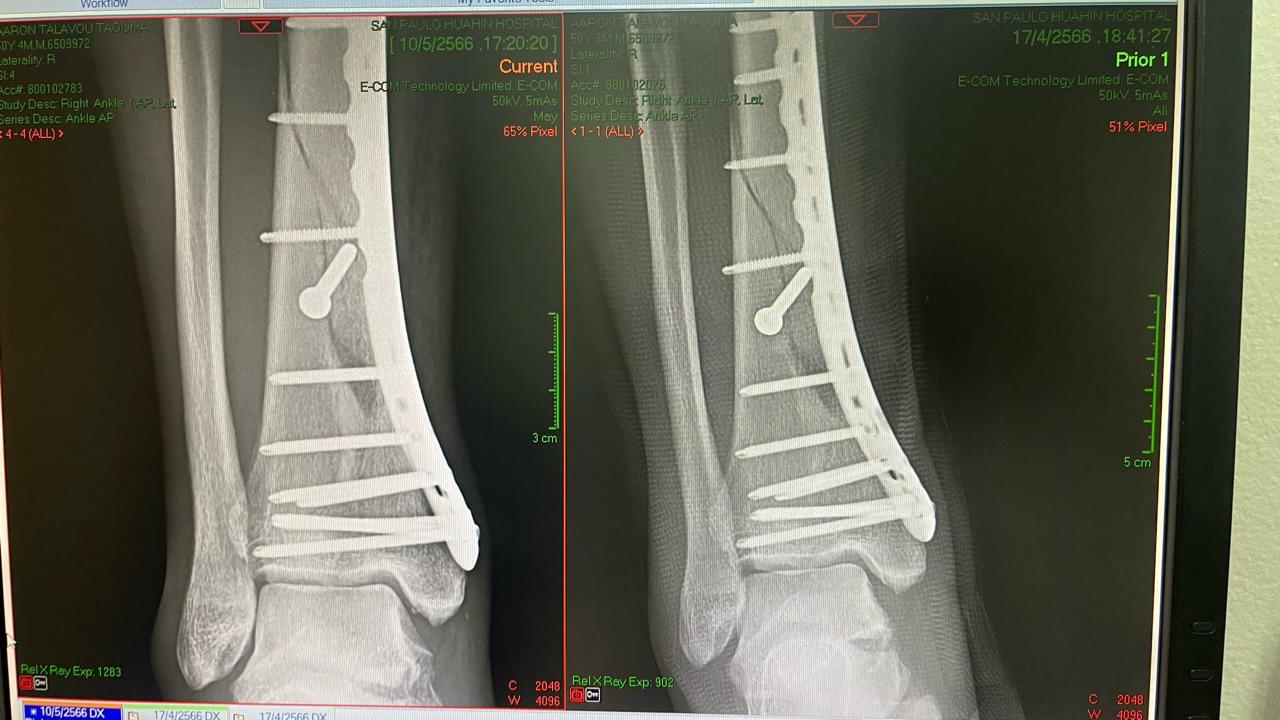

Medical Update  10 May 2023

Had my monthly x-ray and the doc says he reckons it’s 60-70 percent there but healing is a bit slow - reminded me to have no weight baring (only 10-15 %) damn I had started standing and doing small skip walks in my room. He says I still have to be weary and side on caution with use of crutches and elevating leg more and even using a heat pack in the evenings.